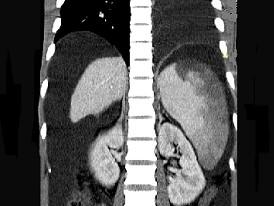

问题 患者男,29岁,乙肝病史10余年,腹胀,有移动性浊音,影像检查如图,最全面的诊断是 ( )

选项 A.肝硬化 B.肝硬化腹水 C.肝硬化腹水、脾梗、胆囊结石 D.大网膜膈下间位及脾梗 E.胆结石及脾梗

答案 C